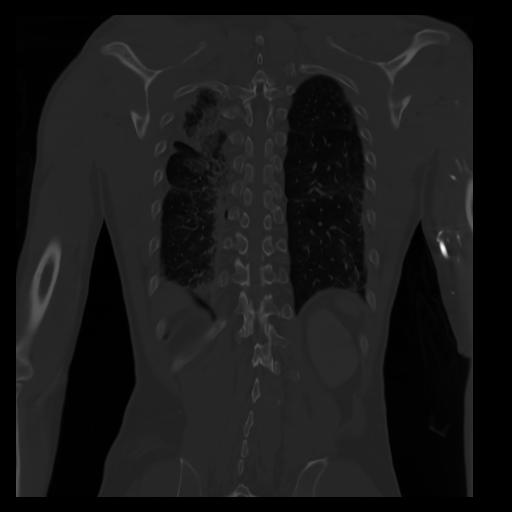

29 CUERPO,CE,Coronal,3.000,CUERPO,Coronal,